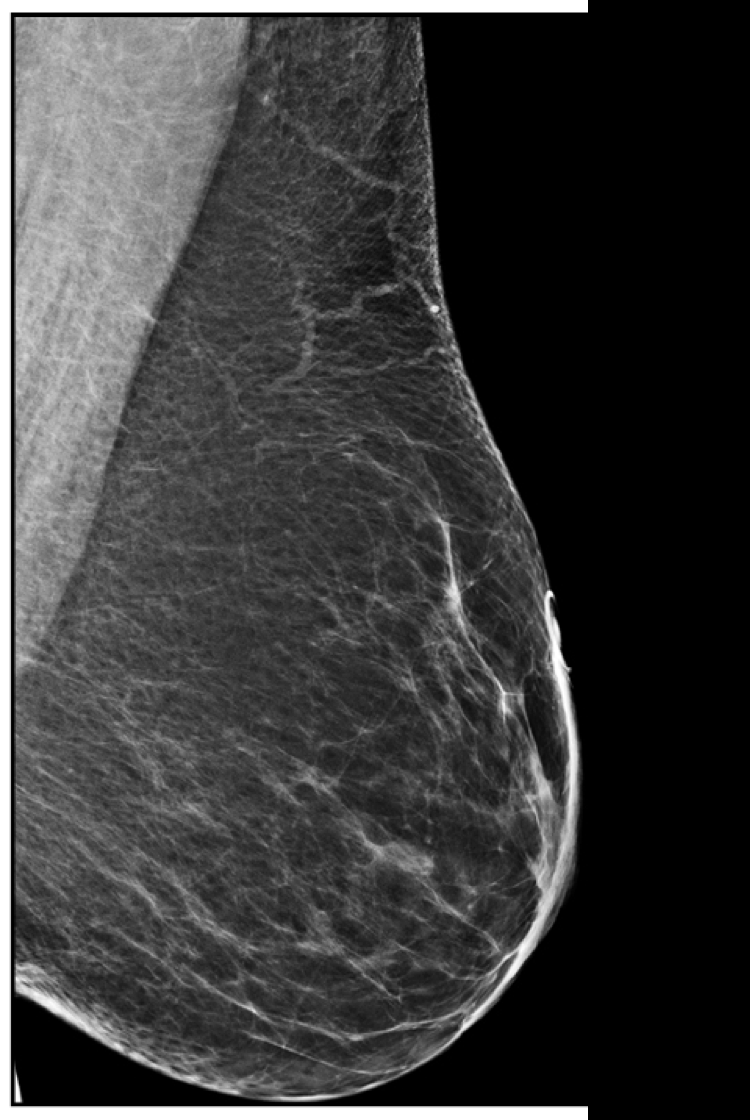

Craniocaudal Cc View And Mediolateral Oblique Mlo View Of Left Download Scientific Diagram

Mammography Views Radiology Reference Article Radiopaedia Org

Mammography Radiology Key

Mammographic Technique And Image Evaluation Radiology Key